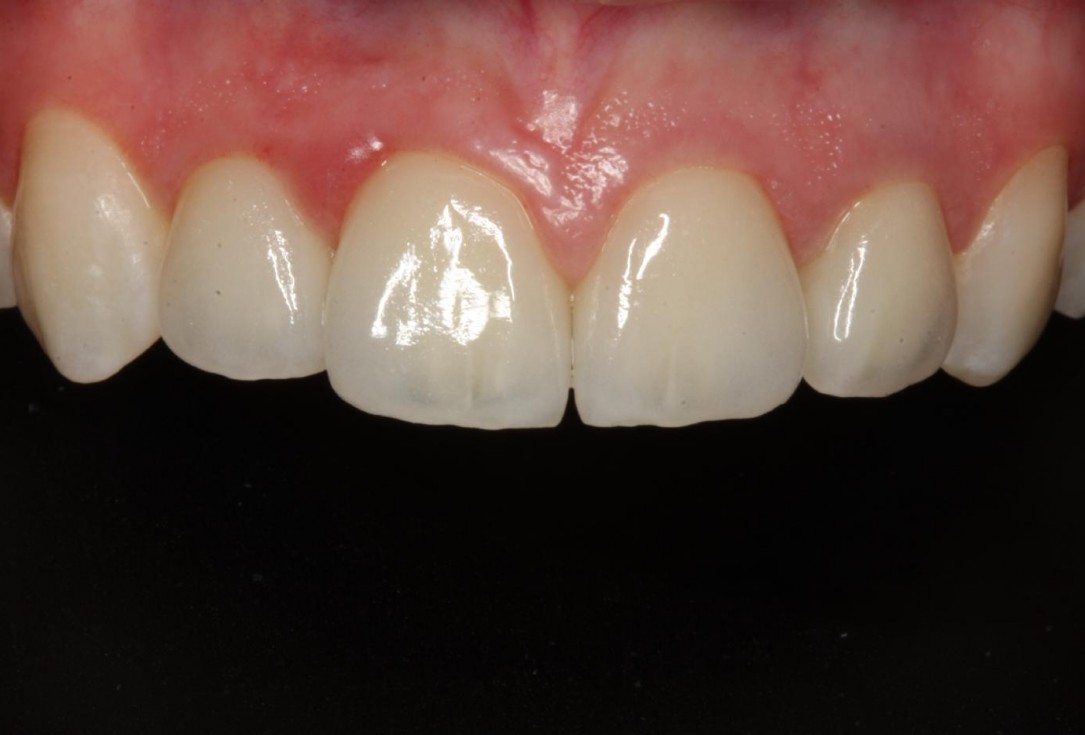

1/12 - Initial clinical situationSoft tissue thickening at immediate implant placement and GBR with mucoderm® and maxgraft® - Dr. A. Puisys

Initial view of the case. Discoloration of 1.1 and mild class I gingival recession

Initial clinical situation with Miller class 1 recession

Initial clinical situation

Initial clinical situation showing strongly compromised tooth 21